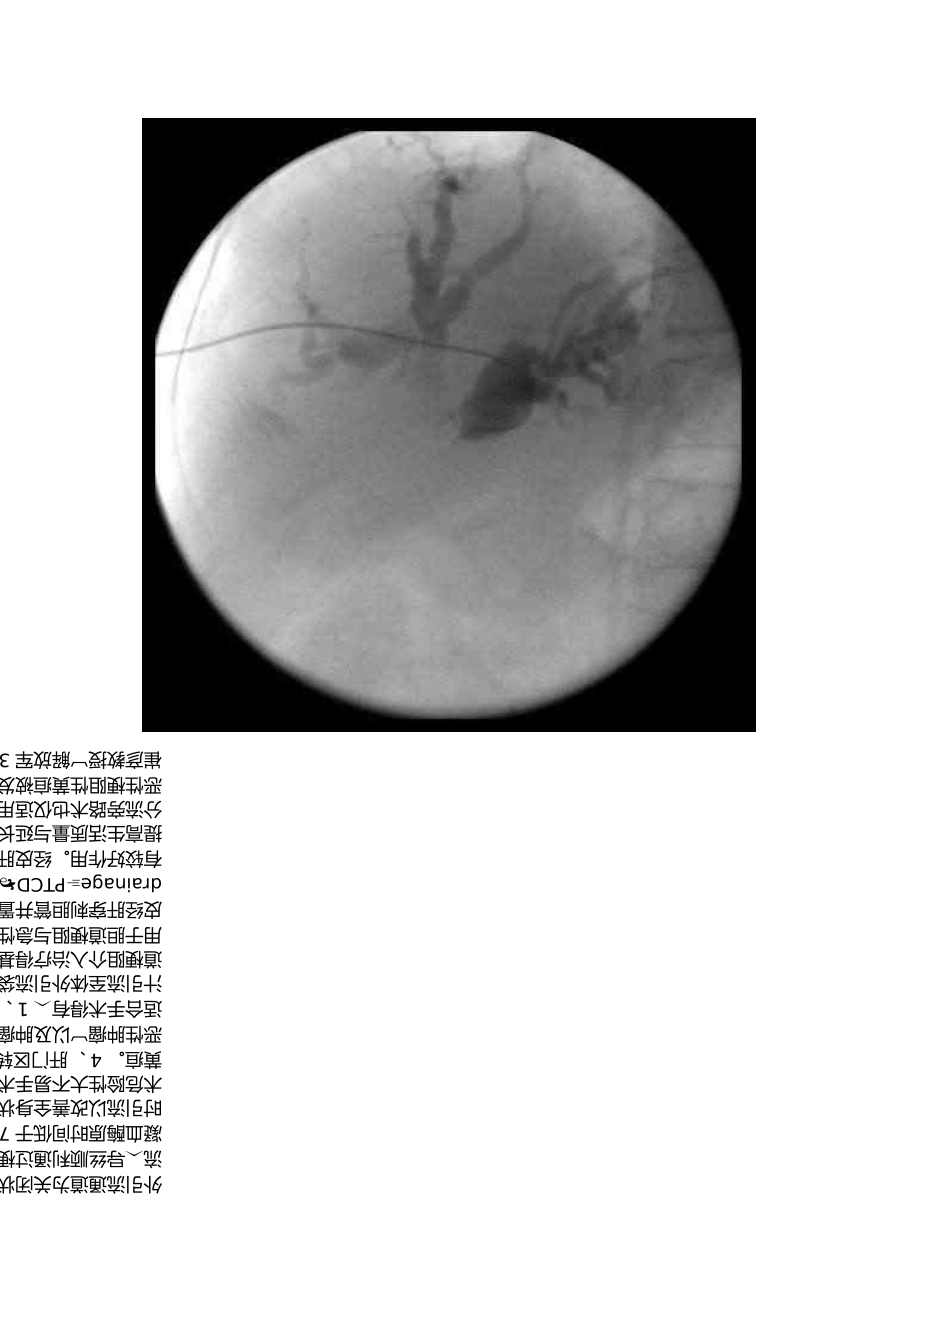

PTCD- 经皮肝穿胆道引流术2016-12-2708:20崔彦教授解放军306 医院普外科恶性梗阻性黄疸被发现时多已晚期据统计其中只有7% 能作外科根治术姑息分流旁路术也仅适用于其中 19% 得病例。临床为改善恶性梗阻性黄疸患者症状、提高生活质量与延长生命经皮穿肝内胆管引流术 PTCD 及胆管内支架置放术有较好作用。经皮肝穿胆道引流术 percuteneoustranshepaticcholangiodrainagePTCD 就是指在影像设备通常为DSA 下 X 线透视或 B 超引导下经皮经肝穿刺胆管并置入引流管使胆汁流向体外或十二指肠得一系列技术。主要用于胆道梗阻与急性炎症得治疗。包括外引流、内引流与内外引流就是所有胆道梗阻介入治疗得基本技术。外引流当引流管不能或不必通过梗阻部位将胆汁引流至体外引流袋。肝门部梗阻或化脓性胆管炎可多支引流。内外引。适合手术得有 1 、手术不能切除得恶性梗阻性黄疸如胰腺癌。2 、原发性胆系恶性肿瘤以及肿瘤已侵犯到肝门部胆管汇与处。3 、中晚期肝癌造成得梗阻性黄疸。 4 、肝门区转移性肿瘤、肿大淋巴结压迫胆总管。 5 、各种因素致使外科手术危险性大不易手术者。如年老体弱心肺功能不全等。6 、外科手术前作暂时引流以改善全身状况为手术作准备。禁忌手术得情况有 1 、凝血机制差凝血酶原时间低于 70% 。 2 、脓毒血症。 3 、大量腹水。 4 、终末期病人。流导丝顺利通过梗阻进入十二指肠采用内外引流管将胆汁引流至肠道。通常外引流通道为关闭状态留作冲洗与后续治疗用一、引导设备1 、 DSA 下 X 线透视传统仍然就是主要手段。优点引导手术全过程可实时动态监视导管、导丝得走向。缺点辐射损害、需要盲目试穿。2 、 B 超引导优缺点与上相反。3 、 B 超透视 B 超引导胆管穿刺可视性与准确性好后续操作透视得优点可发挥。缺点设备依赖性强。二、适应证与禁忌证1 、适应证1 、 1 晚期肿瘤引起得恶性胆道梗阻行姑息性胆道引流。1 、 2 深度黄疸病人得术前准备包括良性与恶性病变。1 、 3 急性胆道感染如急性梗阻性化脓性胆管炎行急症胆道减压引流使急症手术转为择期手术。1 、 4 良性胆道狭窄经多次胆道修补胆道重建及胆肠吻合口狭窄等。1 、 5 通过引流管行化疗、放疗、溶石、细胞学检查及经皮行纤维胆道镜取石等。2 、禁忌证2 、 1 对碘过敏有严重凝血机能障碍、初学倾向严重...